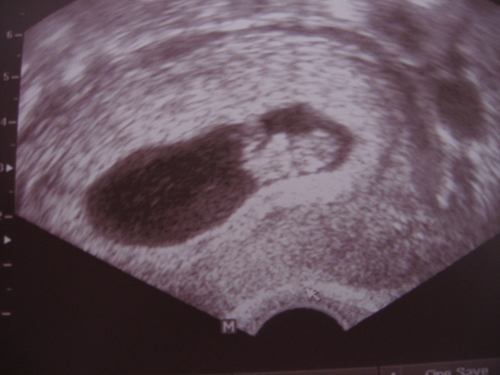

A kaális doki írt fel fogamzásgátlót, átnézte a leleteinket és az mondta, hogy jó, hogy ez a laparos műtét megtörtént, az endot eltávolították és szabaddá tették a jobb oldali pet.-kemet (ami a lombik szempontjából nem, de a spontán próbálkozásnál ez mindenképpen nagyon pozitívat jelent). Írt fel egy havi fogigátlót (amit remélem nem kell elkezdenem szedni) és megkérdezte, hogy eszkimóbabás vagy friss embrió beültetést szeretnék-e, mert a novemberi beültikor két babykénket lefagyasztották. Mi a friss embrió beültetés mellett döntöttünk.

Az endo visszatérése miatt sürget minket az idő, így a doki júniusban vagy júliusban el is kezdené a programot, de előtte még méhtükrözésre mindenképpen el kell mennem, mert azt mondta, hogy ez a leletem már elég régi.

Evvel eddig nem is lenne gond. De mivel mostanában túl sokszor műtöttek (tavaly szeptemberben epekővel, novemberben lombik és most év elején laparom volt), csak olyan méhtükrözéses beavatkozás jöhet szóba, amikor is nem altatnak, mert a lombikkor is altatni fognak. Én őszintén szólva nem is tudtam ilyen altatás nélküli beavatkozásról, pedig van. Magándokihoz kell mennem és a beavatkozás után haza is mehetek. Ha ez a leletem megvan, akkor indulhatunk.